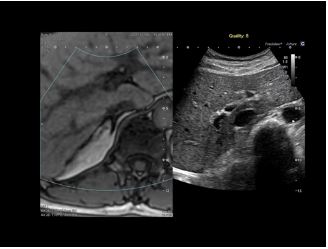

3D MPR зображення матки в трьох площинах з високою роздільною здатністю дозволяє клініцистам оцінити порожнину матки.

Завдяки спеціальним інструментам візуалізації та навігації Aplio також можна інтегрувати з інтервенційними рішеннями, такими як Alphenix 4D CT, щоб підвищити впевненість і точність інтервенційних процедур і подальшого спостереження.